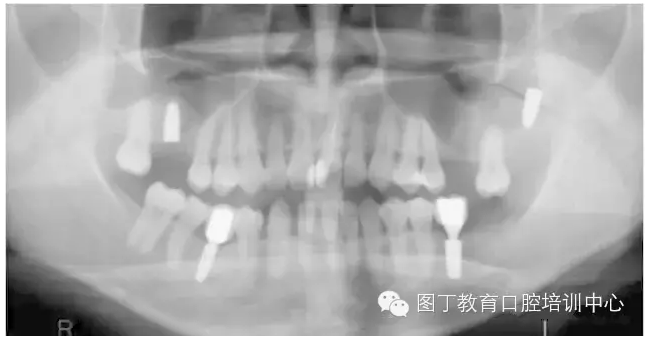

病例8 多顆種植體植入(圖10)

圖10

病例9 種植體進入額竇腔內(nèi)(圖11)

圖11

④種植體植入上頜竇或其他竇腔的情況較少見,但可能在患者為Ⅳ類骨或骨量少時發(fā)生,5~6mm骨量時也可能發(fā)生(如圖11所示)。